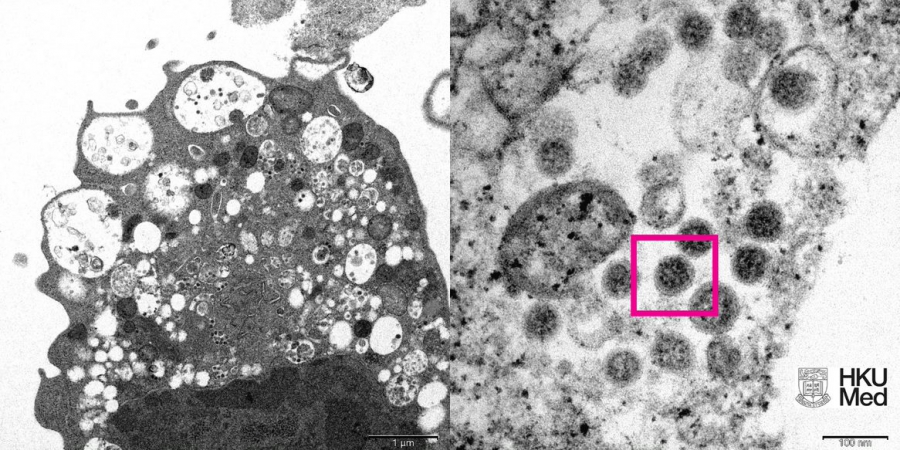

Изследователите са създали електронна микрофотография на кафези (Vero E6) в бъбрека на маймуна, инфектирана с Омикрон. На нея те са видели увреждания с подути везикули, съдържащи вирусни частици. При огромно нарастване учените съумели да разграничат скупчване на присъщи сферични обекти с короновидни шипове на повърхността им.

Снимка: Professor John Nicholls, Clinical Professor of Department of Pathology; and Professor Malik Peiris, Tam Wah-Ching Professor in Medical Science and Chair Professor of Virology, School of Public Health, HKUMed; and Electron Microscope Unit, HKU.